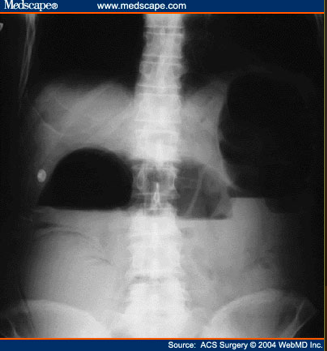

What does this show?

distended small bowel loops

bowel wall b/w loops is thickened and edematous (large white arrow)

No air is seen in the colon or rectum